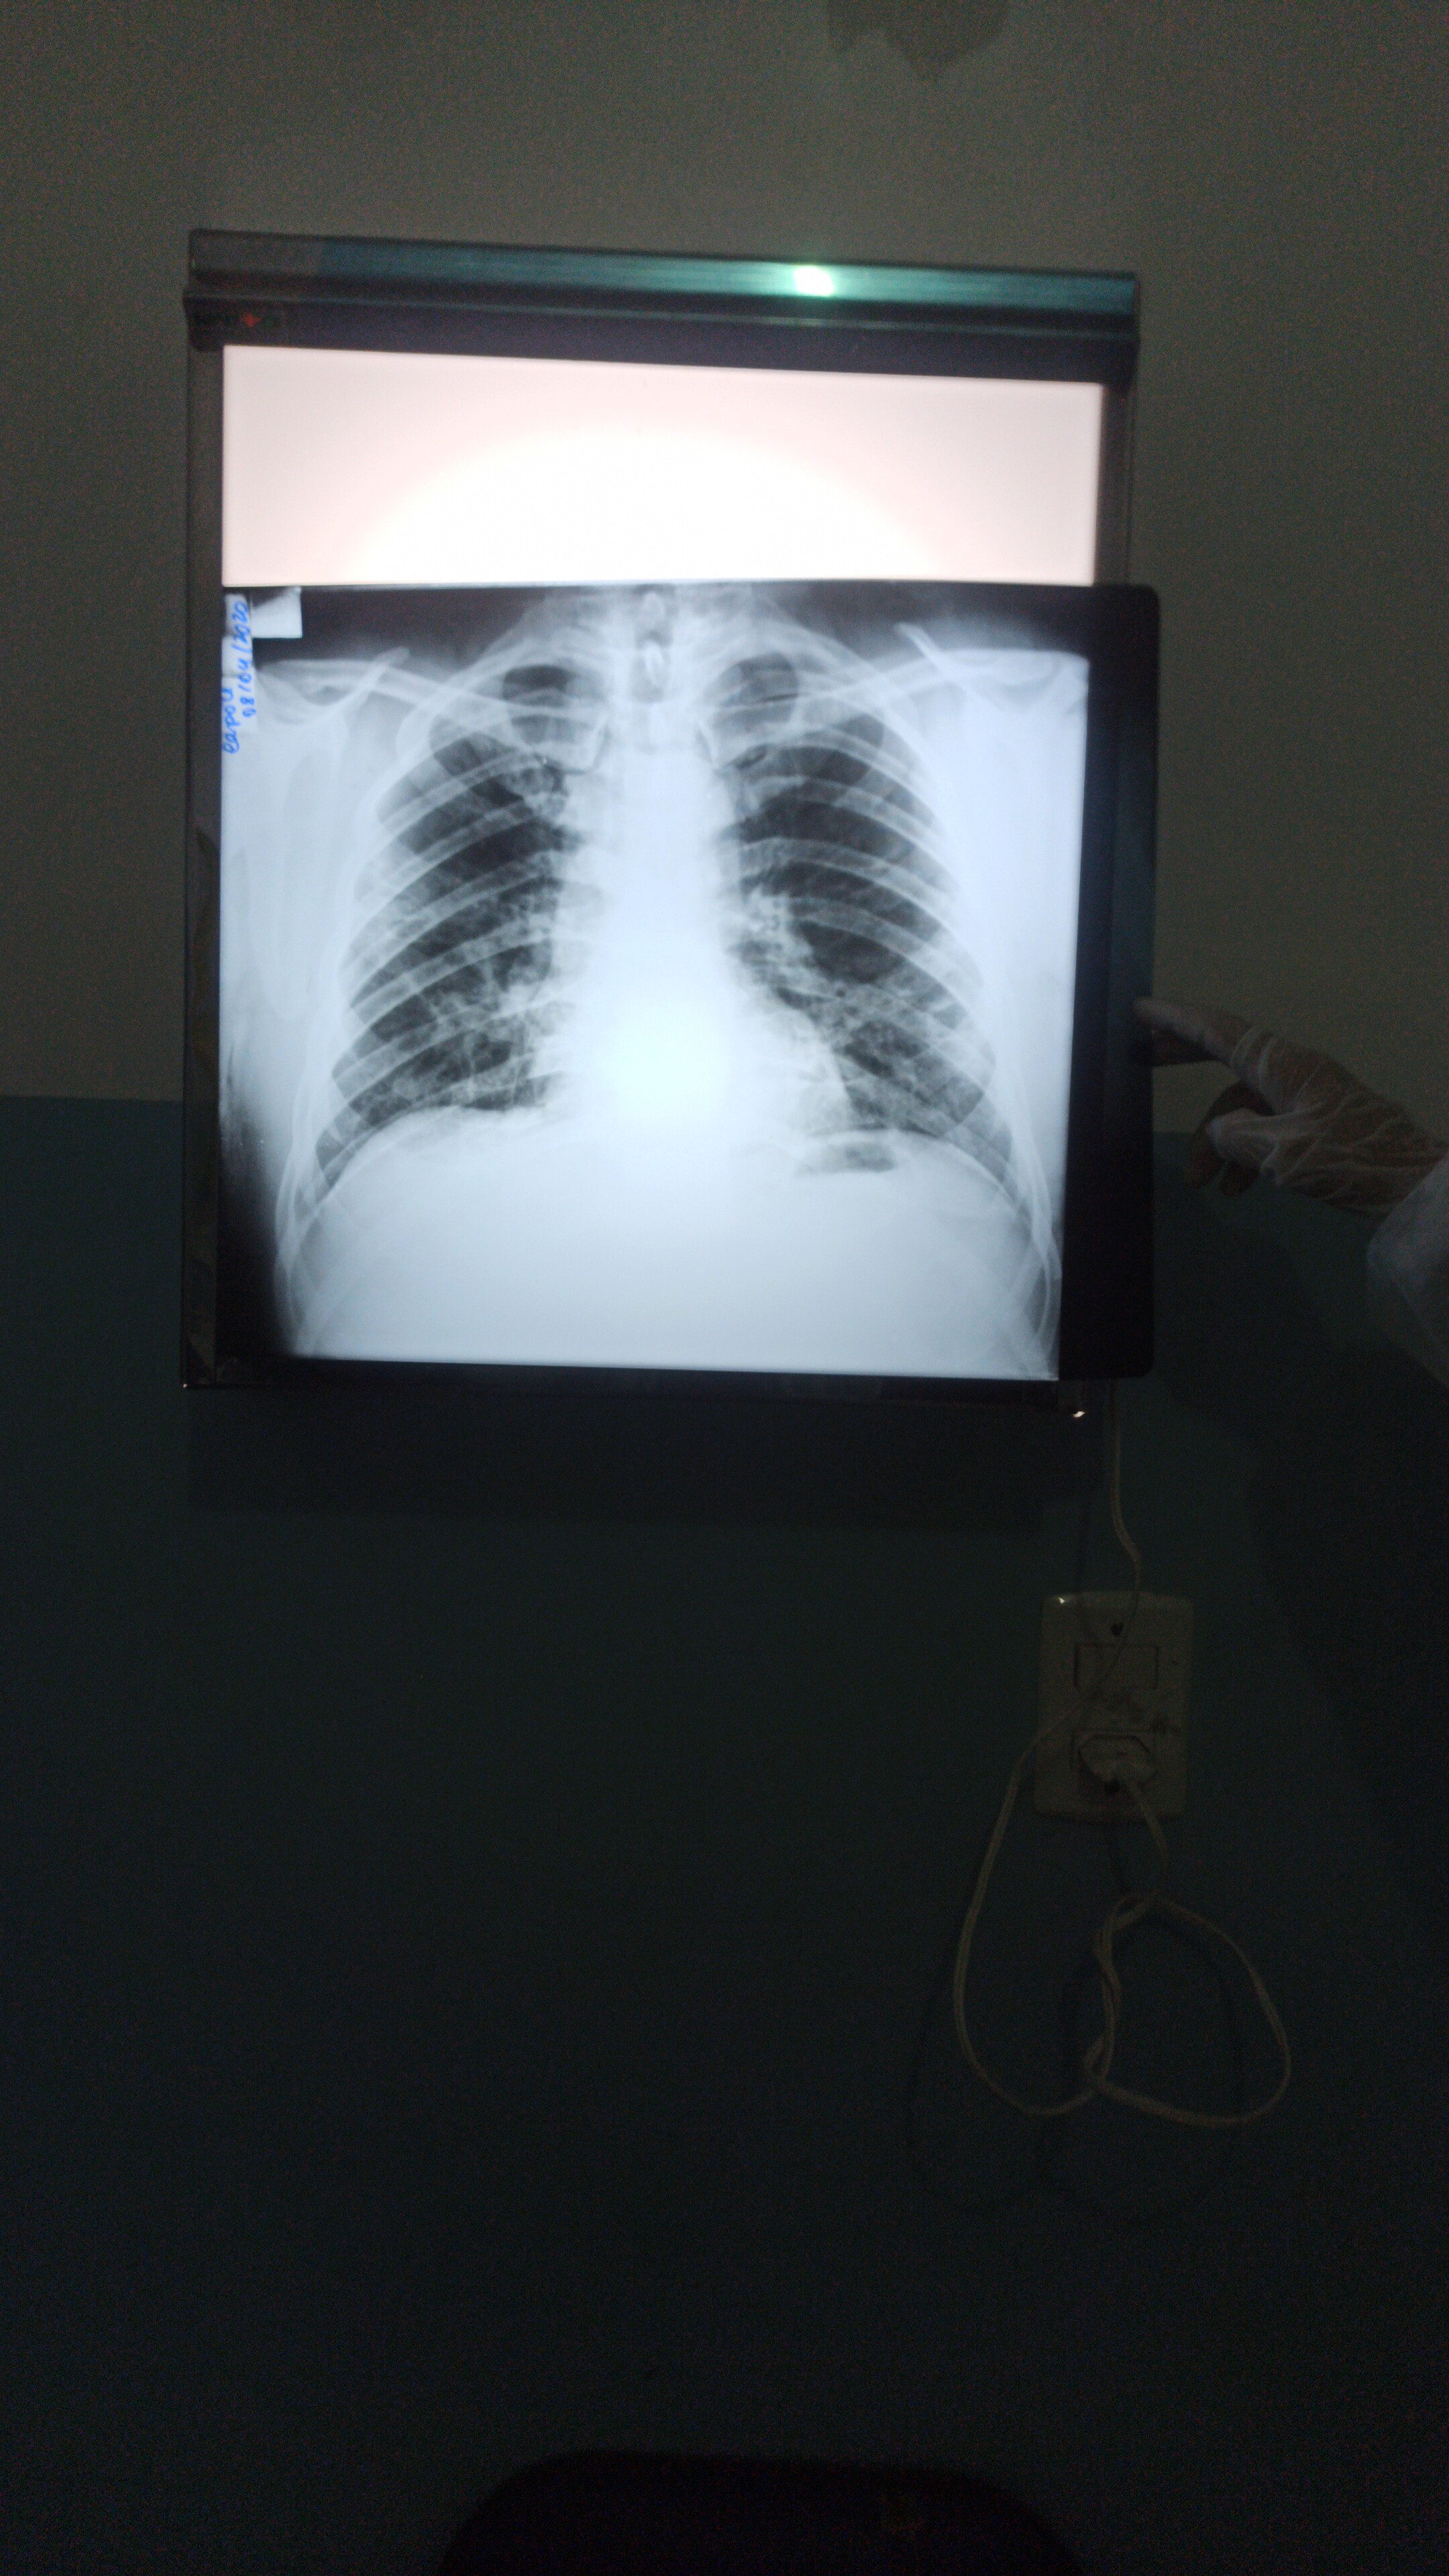

Demanda: Estudo de Caso Clínico (qual o meio de obte-lo: contrato NDA, orçamento?) das análises que fizemos (em anexo) de raio x e tomografia computadorizada obtidos em base pública realizado sob plataforma pública de deep learning com modelo abastecido por datasets públicos de pacientes suspeitos de contágio com covid-19 e outras doenças respiratórias****.

3 - Treinar o Modelo Mellieri Human de Rede Neural Convolucional para detectar o COVID-19 e outras doenças respiratórias em imagens de raios-X e tomografia computadorizada.

4 - Notamos que um paciente pode ter um misto de complicações respiratórias (Covid e Pneumonia por exemplo).

Qual impacto disto nas pesquisas e soluções para combate ao covid-19 como vacinas em função do estágio da doença a exemplo do metadados anexos já que os diagnósticos podem ser únicos para cada paciente no tempo?

Nota: Algumas bases de dados receberam aumento de dados (Data Augmentation) na ausência de um amplo dataset, curiosamente, antes da pandemia atingir o pais 70/80% dos óbitos eram grupo de risco com problemas cardíacos, ao passo que o diagnóstico com emprego de deep learning detect congestive heart failure já é obtido com um único batimento cardíaco de forma que uma única chapa ou tomográfica computorizada, independentemente do estágio, desde que seja positivo covid-19 pode ser empregado como dataset para emprego global de casos, o que não exclui a importância do diagnóstico amplo e diverso a exemplo de casos que combinam covid-19 e outras patologias respiratórias ***